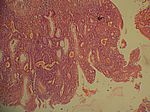

Colitis ulcerosa, HE